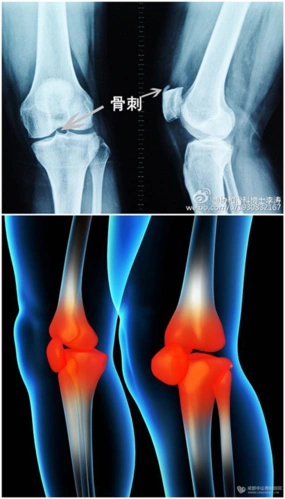

膝盖长了骨刺揉一揉多锻炼能磨掉吗

骨刺能通过锻炼磨掉吗吃药或手术后还会复发吗

膝盖里发现有骨刺,它究竟是什么东西,有害吗?